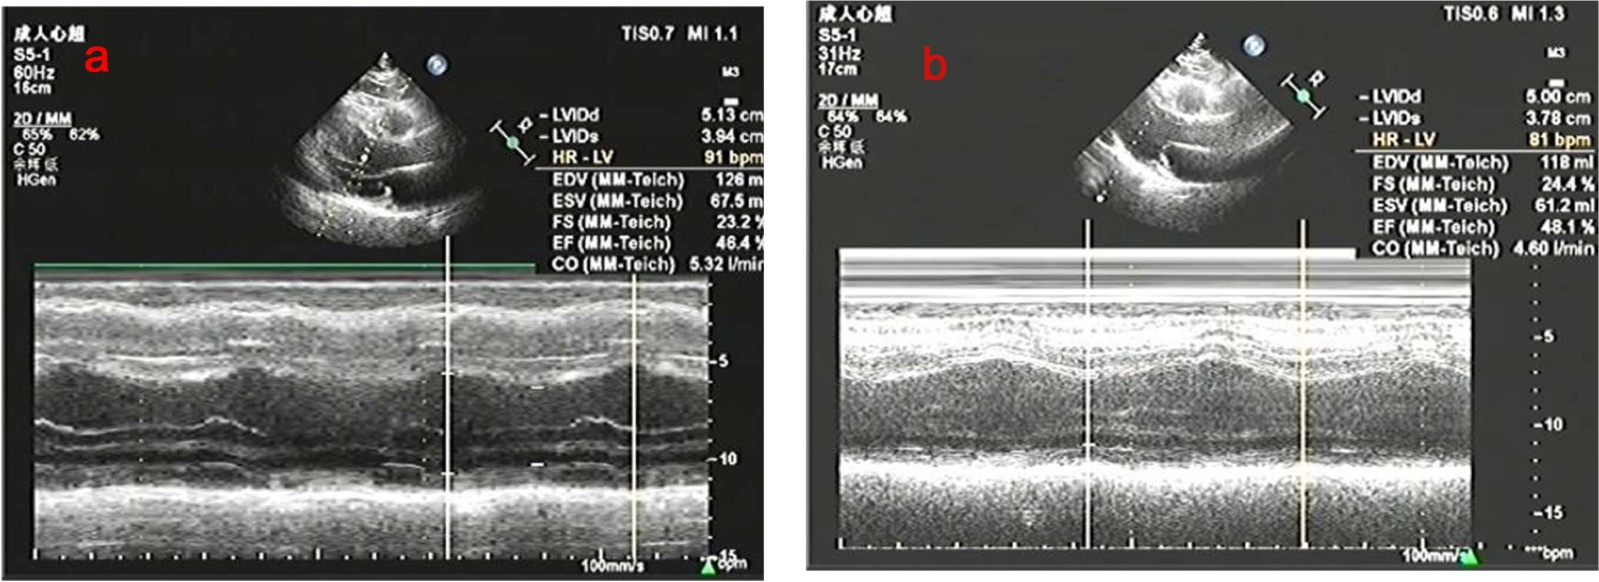

并于出院后2月余再次来我院,复查心脏彩超(见图3),并行冠脉造影(见图4)检查,提示前降支(LAD)近中段弥漫性狭窄约80%~90%,回旋支(LCX)远段弥漫性狭窄约90%~95%,右冠状动脉(RCA)近段狭窄约30%~40%,于回旋支病变处成功行PCI治疗。4月余再次来我院,再次复查心脏彩超(见图3),并行冠脉造影(见图4)检查,LCX支架通畅,于前降支病变处成功行PCI治疗。目前随访,恢复良好。

注:(a) 出院后2个月后复查心脏彩超:EF:46%,阶段性室壁运动异常,左室心尖部室壁瘤形成可考虑,主动脉瓣反流(少量),二尖瓣反流(少量),三尖瓣反流(少量),左室扩大,左心功能减退。(b) 出院后4个月后复查心脏彩超:EF:48%,节段性室壁运动异常(多节段)、左室心尖部室壁瘤形成可考虑、主动脉瓣反流(少量)、左室扩大、左心功能减低。

Figure 3. Follow-up echocardiography

3. 心脏超声随访